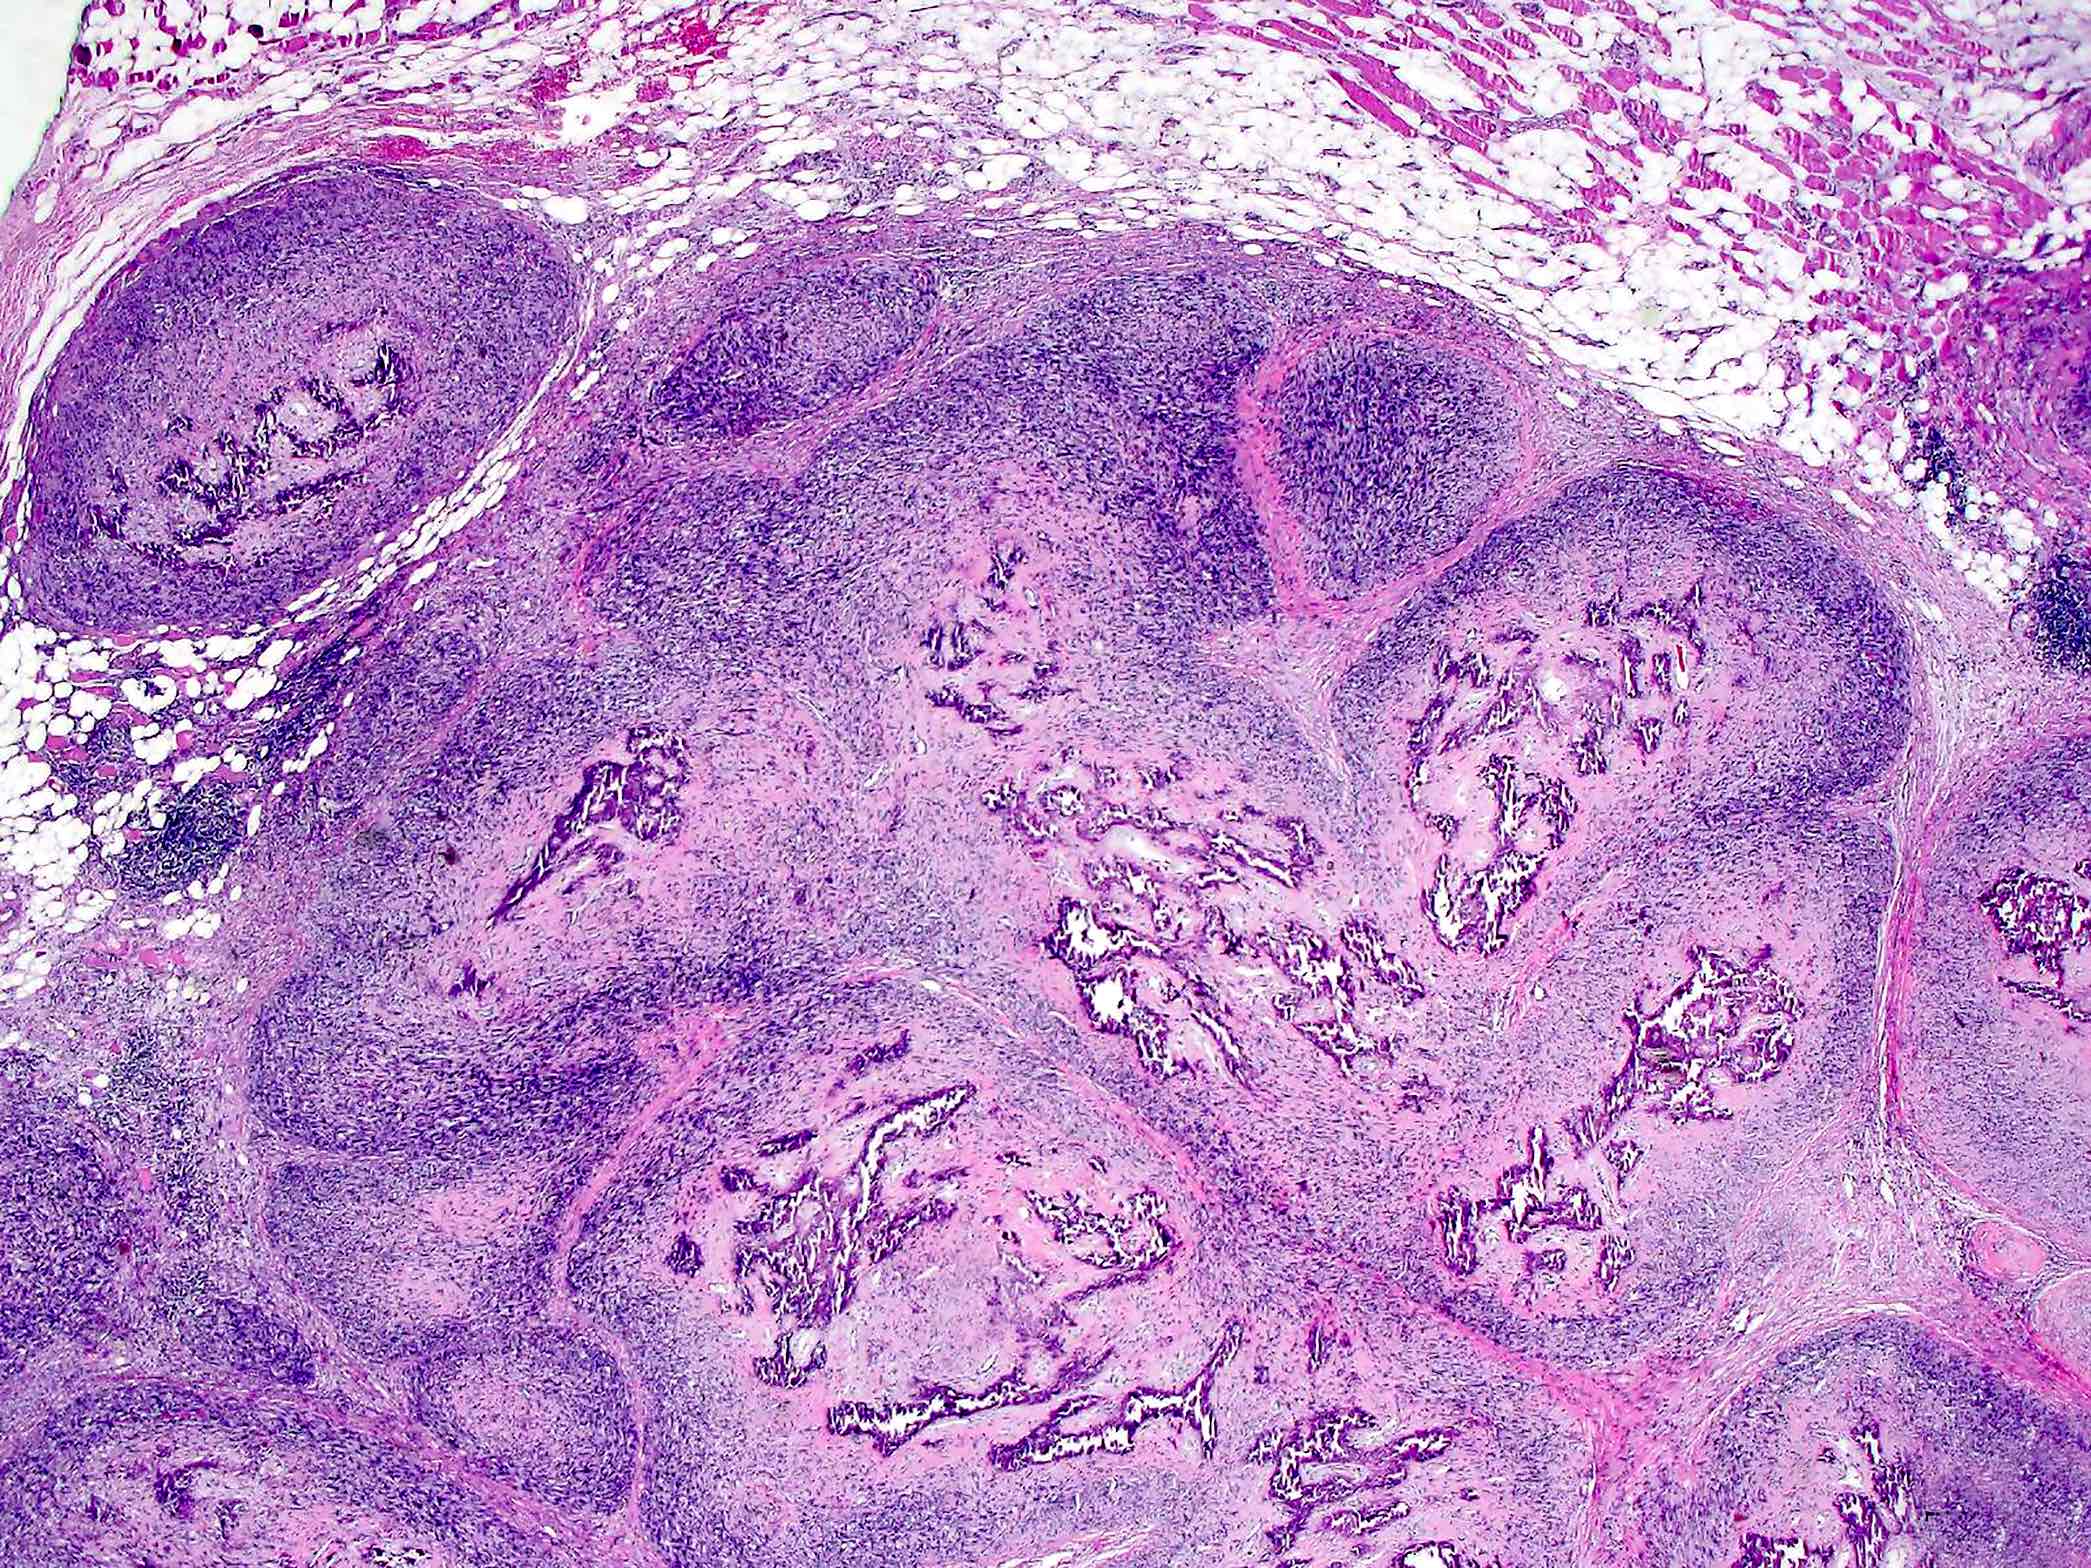

Microscopic (histologic) images

Contributed by Jesse Hart, D.O., Borislav A. Alexiev, M.D. and AFIP

- Periosteal osteosarcoma:

- Ossified mass: intimately attached to native cortex (secondary to endochondral ossification)

- Pericortical bone: dense, mature bone

- Bony spicules: radiate from the dense pericortical bone peripherally and admix with the hyaline cartilage component

- Large vascular cores in center of bony spicules

- Periphery of spicules is calcified / osseous or chondro-osseous and merges with (atypical) hyaline cartilage

- Periphery of mass (majority of the tumor’s volume):

- Atypical hyaline cartilage (appearance of grade 1 - 3 chondrosarcoma); may have myxoid change

- Osseous component (always present but not the dominant component): intermediate grade osteosarcoma intermixed with cartilaginous component; may have lace-like bone but large areas of conventional osteoblastic osteosarcoma are not present

- May have an admixed fibroblastic component (fascicles of mitotically active spindle cells)

- Ossified mass: intimately attached to native cortex (secondary to endochondral ossification)